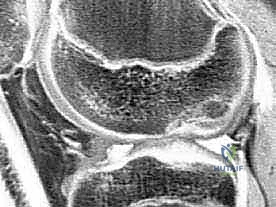

Magnetic Resonance Imaging (MRI)

MRI is our gold standard for cartilage evaluation, boasting high sensitivity and specificity.

* Sequences: Clinically proven cartilage-sensitive sequences include T1-weighted gradient echo with fat suppression and fast spin-echo sequences with and without fat suppression. These protocols allow us to detect full- and partial-thickness lesions, as well as osteochondritis dissecans, even when clinically silent.

* Utility: MRI helps us characterize the lesion size, depth, and the integrity of the subchondral bone, which is vital for surgical planning. It can also detect associated pathologies like meniscal tears or ligament injuries.